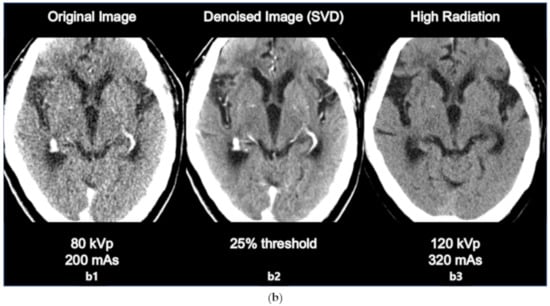

The comparison between original image, denoised image, and high radiation dose image is as in the following Figure 4a,b. The sharpness of ventricle and parenchyma margin, the distinctness of basal ganglia and parenchyma in the denoised image, and the differentiation of gray matter and white matter in the denoised image was clearly described close to original high dose image.

(a) Comparison between the original image (80 kVp, 200 mAs, a1 the denoised image using SVD (25% threshold, a2, and the high dose image (120 kVp, 320 mAs, a3). (b) Comparison between the original image (80 kVp, 200 mAs, b1), the denoised image using SVD (25% threshold, b2), and the high dose image (120 kVp, 320 mAs, b3).

The results of the SNR and CNR estimations are presented in Figure 5a,b. In Figure 5a, the mean SNRs at the basal ganglia level exhibited a significant increasing tendency except for the 15% and 30% threshold values. The largest improvement involving a significant 16% increase (t = 2.908, p < 0.005) was observed at the 40% threshold setting. Similarly, in Figure 5b, the mean CNRs at the basal ganglia level maintained an increasing tendency for every threshold setting. The largest improvement involving a significant 43% increase (t = 6.327, p < 0.001) was also observed at the 40% threshold setting. However, image a6 that is labeled as 25% of the threshold value resulted in the best statistical significance per the results of the paired t test (t = 3.764, p < 0.001), resulting in an adequate 14% increase in the SNR. Considering the example dataset presented in Figure 3a, even though the 40% setting resulted in the highest SNR, the 25% setting appeared to generate more diagnostic information associated with the vessels. The 25% setting also resulted in good CNR estimation results with a statistically significant 37% increase (t = 6.080, p < 0.001). Based on these findings, we considered that the 25% setting could potentially be the optimal setting for 4D axial CTP images at the basal ganglia level in terms of compromising between noise reduction and preserving diagnostic information. In addition, we would like to highlight that we were able to achieve a considerable improvement in quantitative image quality in the denoised images without having to increase the radiation dose. Figure 4a,b shows the comparison of the original image with the lower dose image (80 kVp, 200 mAs, a1), the denoised image (80 kVp, 200 mAs, 25% of threshold, a2), and the higher dose image (120 kVp, 320 mAs, a3). Regarding Figure 4a,b, we would like to believe that we were able to improve the diagnostic value of low dose (Figure 4a,b, a2, b2) image similar to the ones scanned with high dose (Figure 4a,b, a3, b3) by using the proposed SVD-denoising technique. In other words, there is potential to preserve sufficient image quality even in scans involving lower tube currents. Lowering the tube current and tube voltage is the simplest way to reduce the radiation dose involved in a CT scan. Based on the fact that the amount of noise on an image is inversely proportional to the square root of the radiation dose, reducing tube current and tube voltage can inevitably lead to the degradation of image quality, thereby generating a larger amount of noise on the image [30,31]. Considering this, additional studies to investigate the qualitative and quantitative comparison between the denoised lower dose image and higher dose image on CTP may be meaningful. Additionally, further study with artificial biological objects using 3D bioprinting will be required for more accurate evaluation.